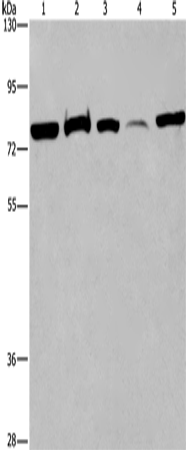

WB Predicted band size: |

58 kDa |

WB Positive control: |

293T cells, human fetal brain tissue and K562 cells, human fetal liver tissue and Hela cells |

WB Recommended dilution: |

500-2000 |